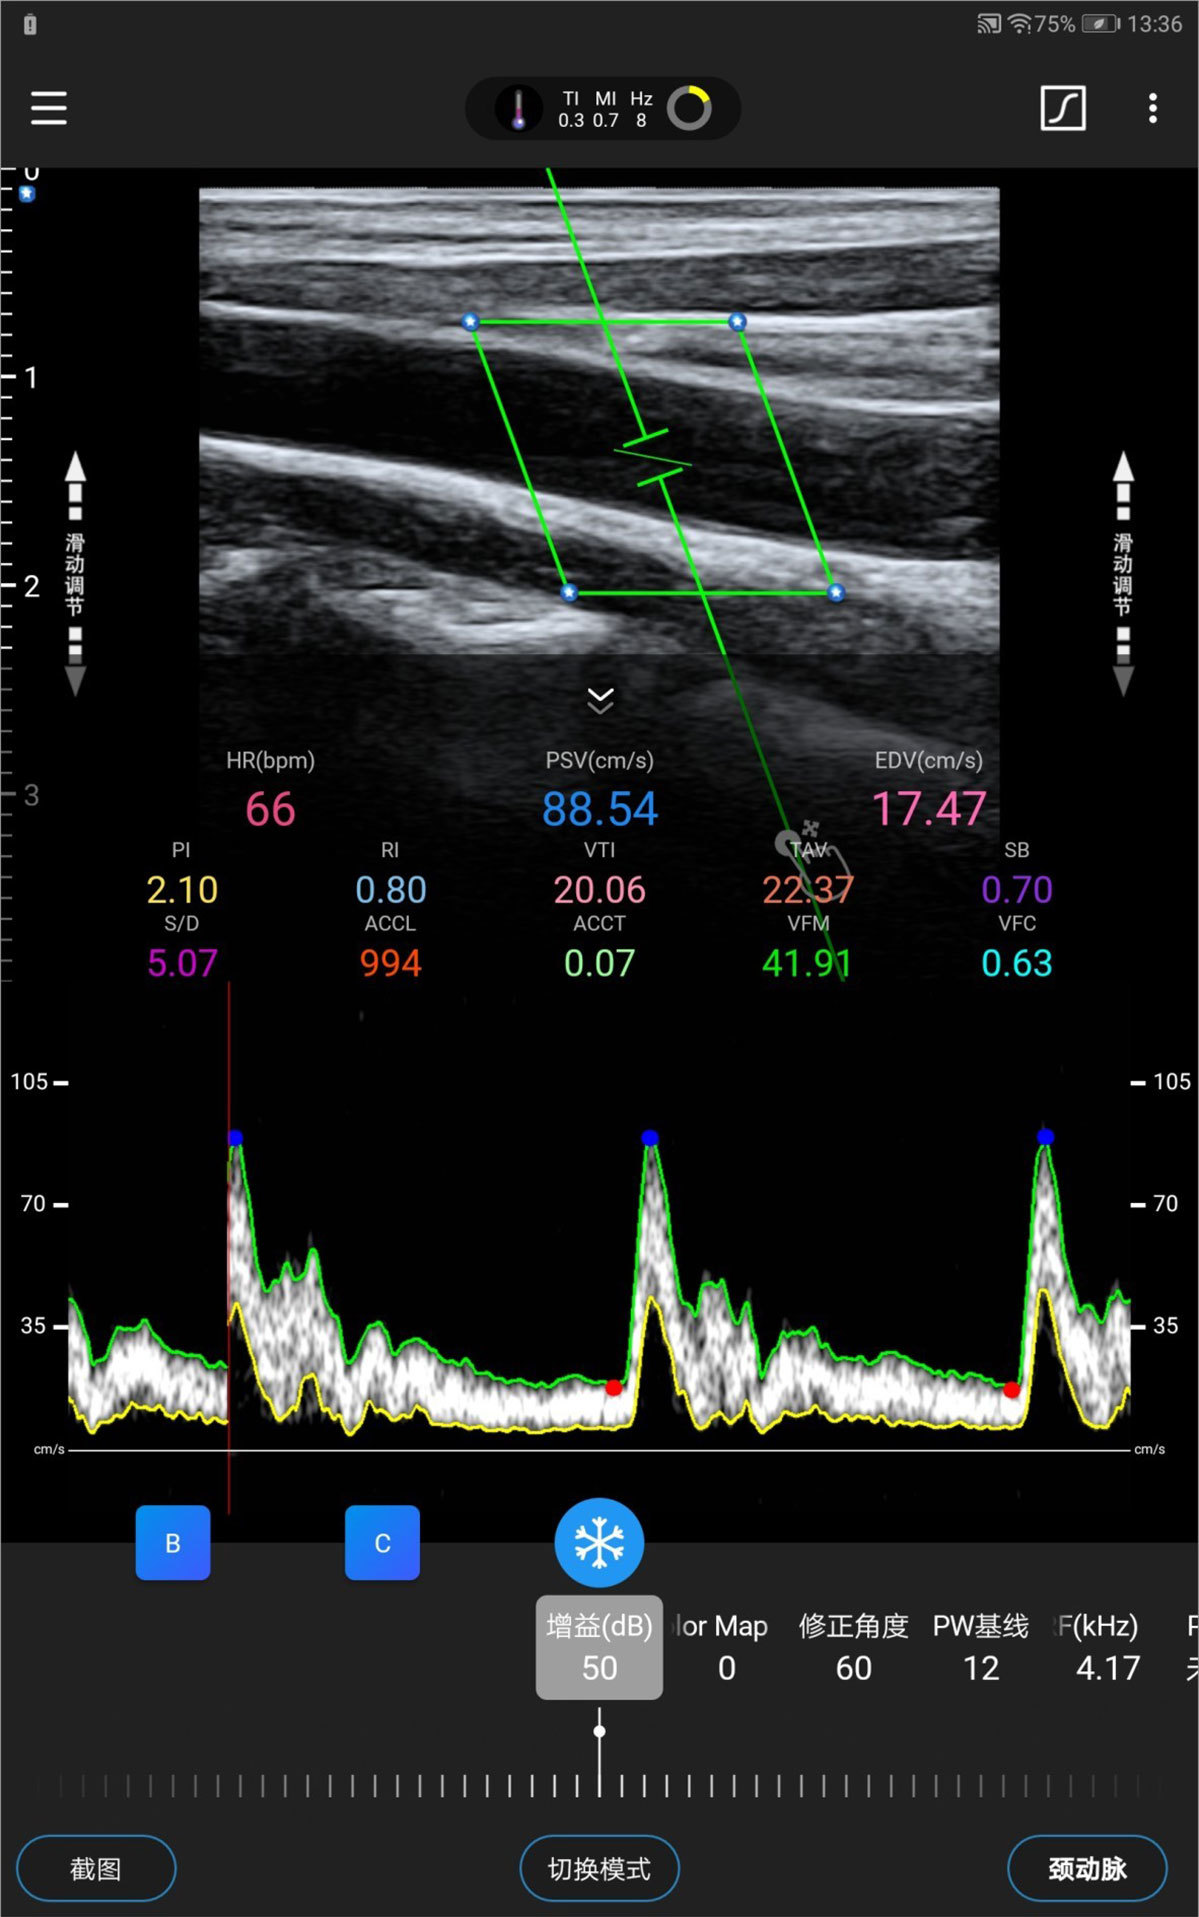

Prueba de prevención cardiovascular

Autorreconocimiento y automedición de IMT

Galería de demostración